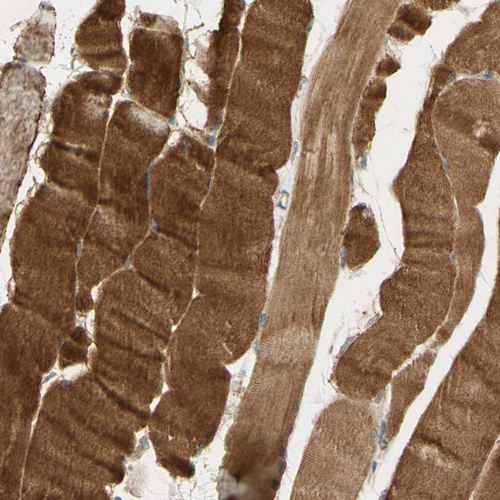

Immunohistochemical staining of human heart muscle shows moderate cytoplasmic positivity in cardiomyocytes.